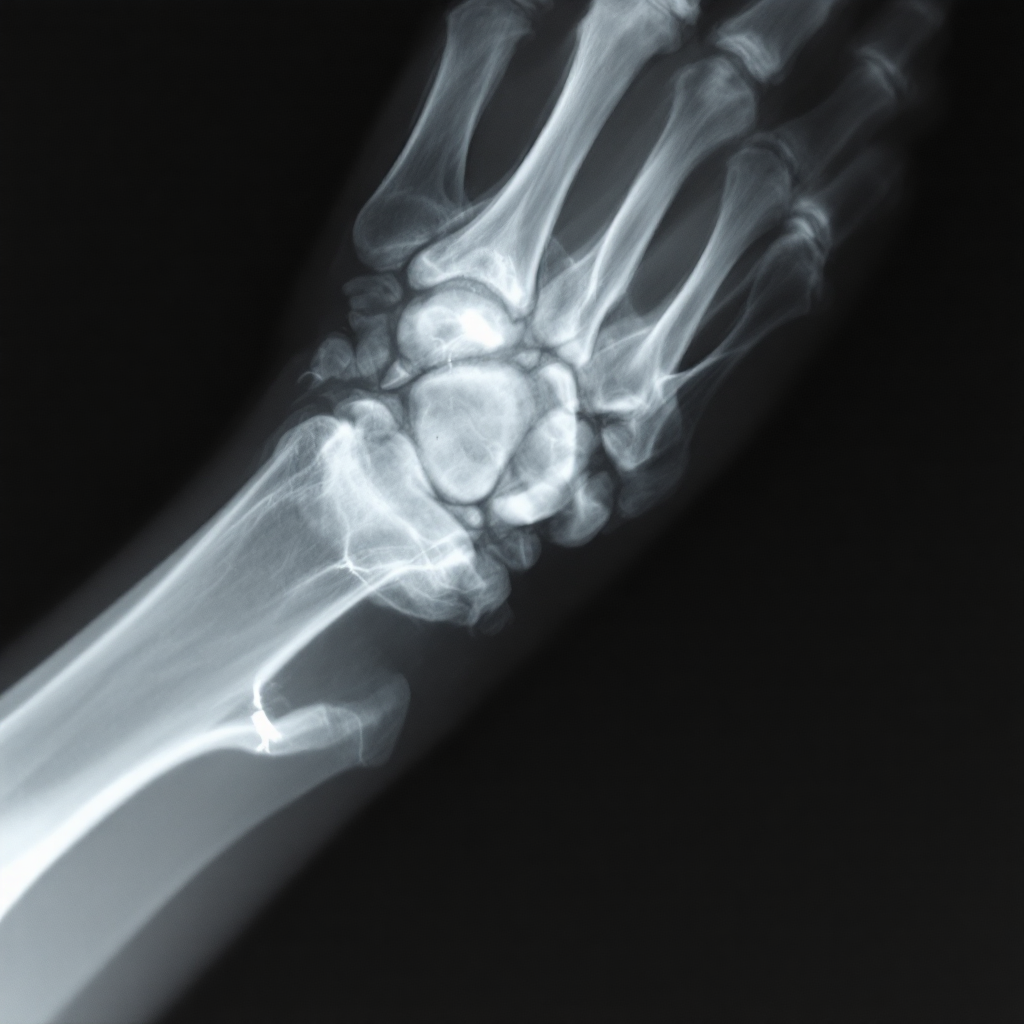

먼저 가장 기본적인 진단 도구는 엑스레이(X-ray)예요. 엑스레이를 통해 뼈에 금이 갔는지, 골절이 어느 정도인지, 뼈가 어긋나 있는지를 확인할 수 있어요. 특히 골절 선의 위치나 파편 여부도 판단할 수 있기 때문에 진단의 첫 단계로 꼭 필요해요.

엑스레이로는 골절이 명확히 보이지 않는 경우도 있어요. 이런 때는 CT(컴퓨터 단층촬영)나 MRI를 활용하게 돼요. 특히 관절 가까운 부분이나 미세 골절, 연골 손상 여부까지 확인할 수 있어서 더 정밀한 진단이 가능해요.

| 엑스레이 (X-ray) | 골절의 유무 및 뼈 어긋남 확인 | 기본적이고 빠름 |

| CT 촬영 | 미세 골절, 뼈의 세부 구조 파악 | 고해상도 이미지 제공 |

| MRI 검사 | 인대, 힘줄, 연골 손상 확인 | 연부조직까지 확인 가능 |

| 촉진 검사 | 의사가 손으로 눌러 통증 위치 확인 | 신속한 1차 판단 도구 |